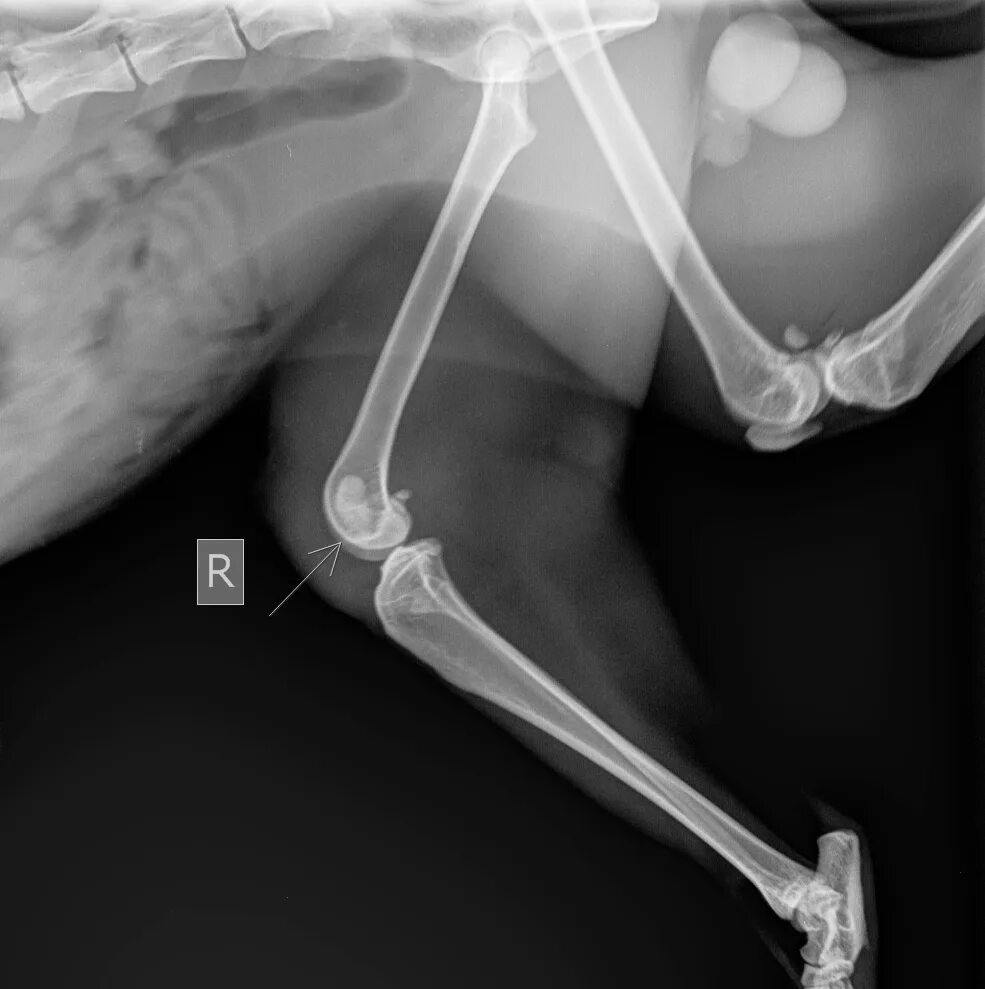

Операция суставов собак